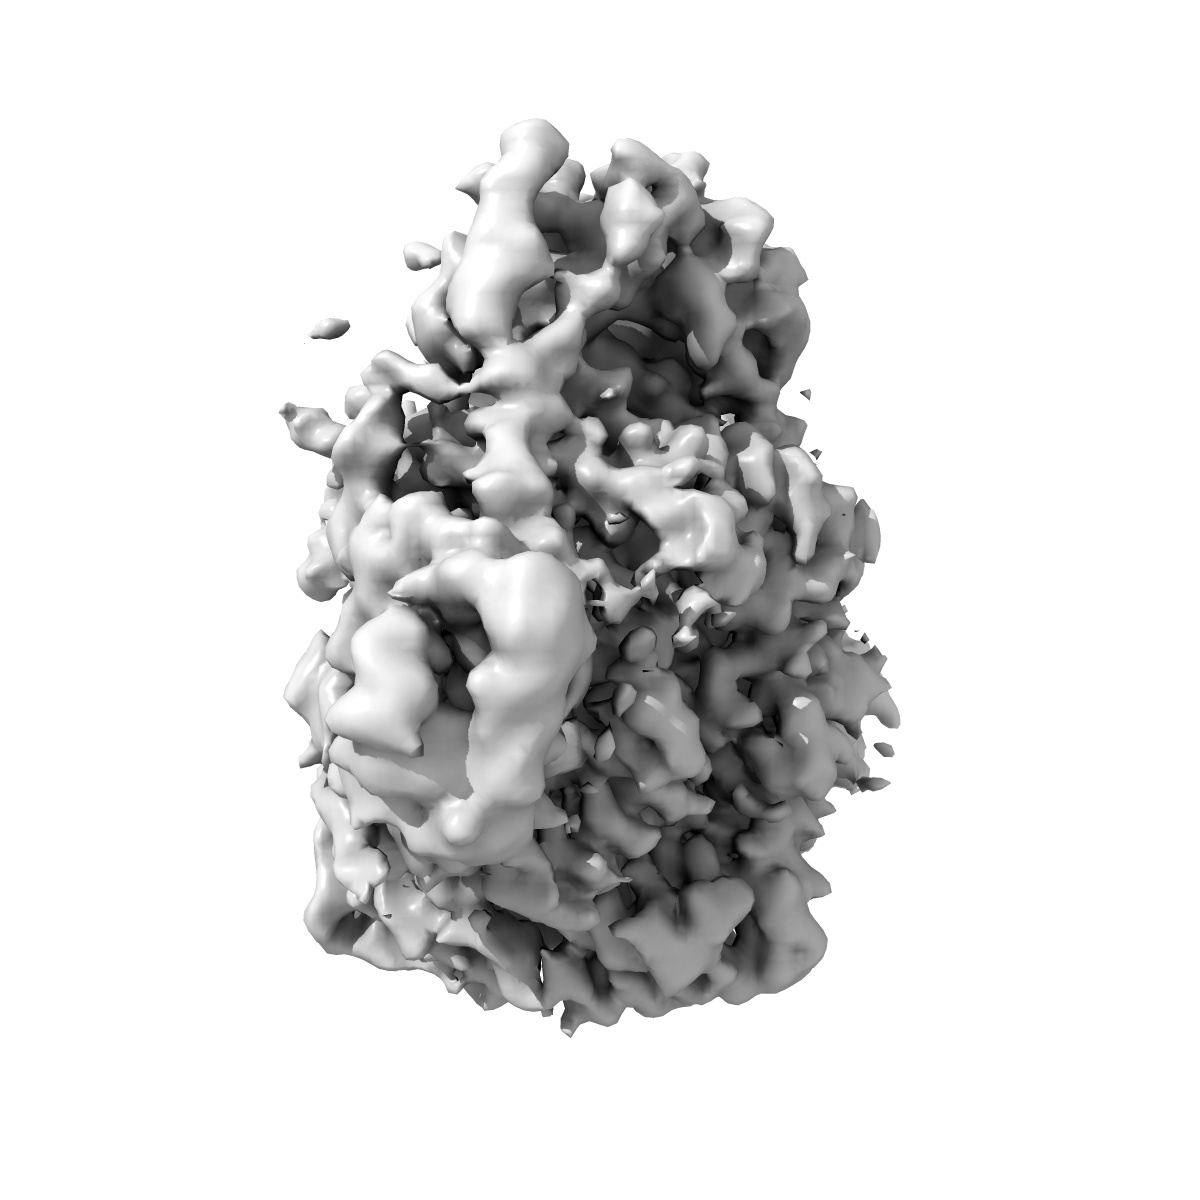

EMD-48721

Cryo-EM Structure of HIV-1 Reverse Transcriptase p66 tetramer in Complex with 5-{2-[2-(2-oxo-4-sulfanylidene-3,4-dihydropyrimidin-1(2H)-yl)ethoxy]phenoxy}naphthalene-2-carbonitrile (JLJ648), a Non-nucleoside Inhibitor

Single-particle3.43 Å

Fitted models: 9mxt